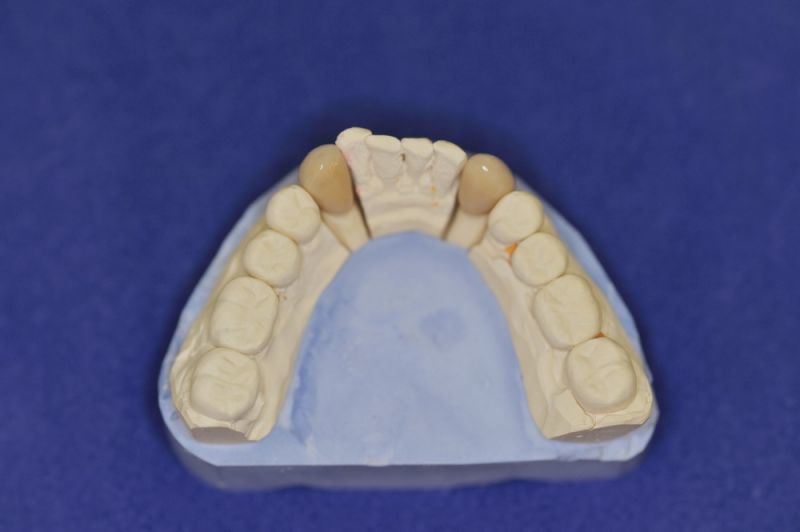

Der Patient erhält die beiden letzten Kronen zur Einstellung der dynamischen Okklusion.

In diesem Fall möglich über die Herstellung von zwei Eckzahnkronen

Das Weihnachtsgeschenk des Patienten nach zweieinhalb Jahren zahnärztlicher Funktionsdiagnostik und -therapie.